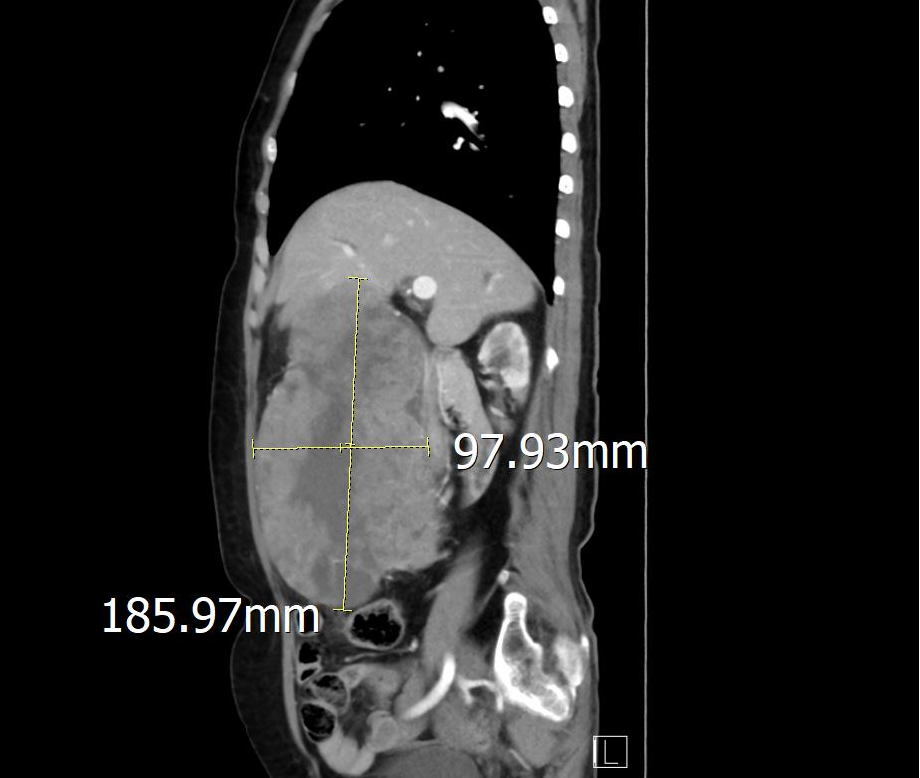

三年前,文婆婆在体检时发现胃部有一大小约2.5cmx2.4cm的包块占位,没有任何的不适,故未引起重视。一个月前,文婆婆发现肚子变大,并且摸到了一个大包块,还经常有黑便,多次出现头晕眼花乏力等症状。为了搞清楚病因到我院普通外科就诊,经完善CT提示腹腔巨大占位性病变,大小约14.7x9.6x15.7cm。

腹部CT

通过CT图像清楚发现肿瘤已经明显增大,在完善相关辅助检查后,发现文婆婆还存在严重的贫血,粪便隐血呈强阳性,这一切都提示肿瘤正在出血。